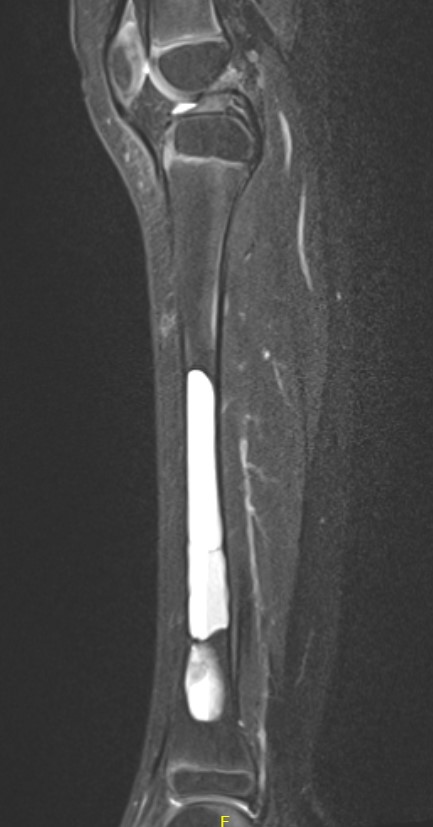

MRI

Gruenewald et al Br J Radiol 2023

- 36 patients with UBC or ABC

- fluid fluid levels / septation seen in both

- arterial feeders on MRA helped differentiate some ABC's

Surgical cyst drainage using implants

Concept

- venous hypertension cause of cyst

- if allow cyst to drain, will heal

Options

- cannulated screws in calcaneum

- flexible nails humerus

- intramedullary nail femur